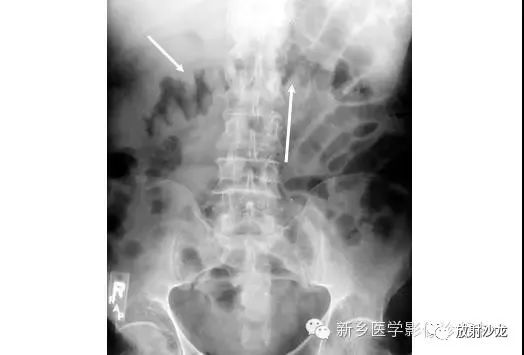

这例腹痛患者的主要异常在哪里?

该X光片显示伪膜性肠炎患者结肠袋广泛增厚(箭头)。结肠袋是结肠上小的囊袋状突起,这种分段的外观可以有助于在X线平片上区分小肠与结肠。伪膜性肠炎中,增厚的肠壁是由肠壁水肿引起的。典型的表现是结肠扩张、呈结节状增厚的结肠袋和拇指印。此X线片横结肠明显增厚。

钡剂灌肠进一步突出结肠袋增厚。